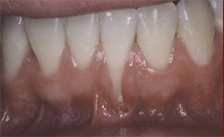

Before and After Pictures of Three Cases of Recession Treated with Soft Tissue Grafting

Case #1

| BEFORE | AFTER |